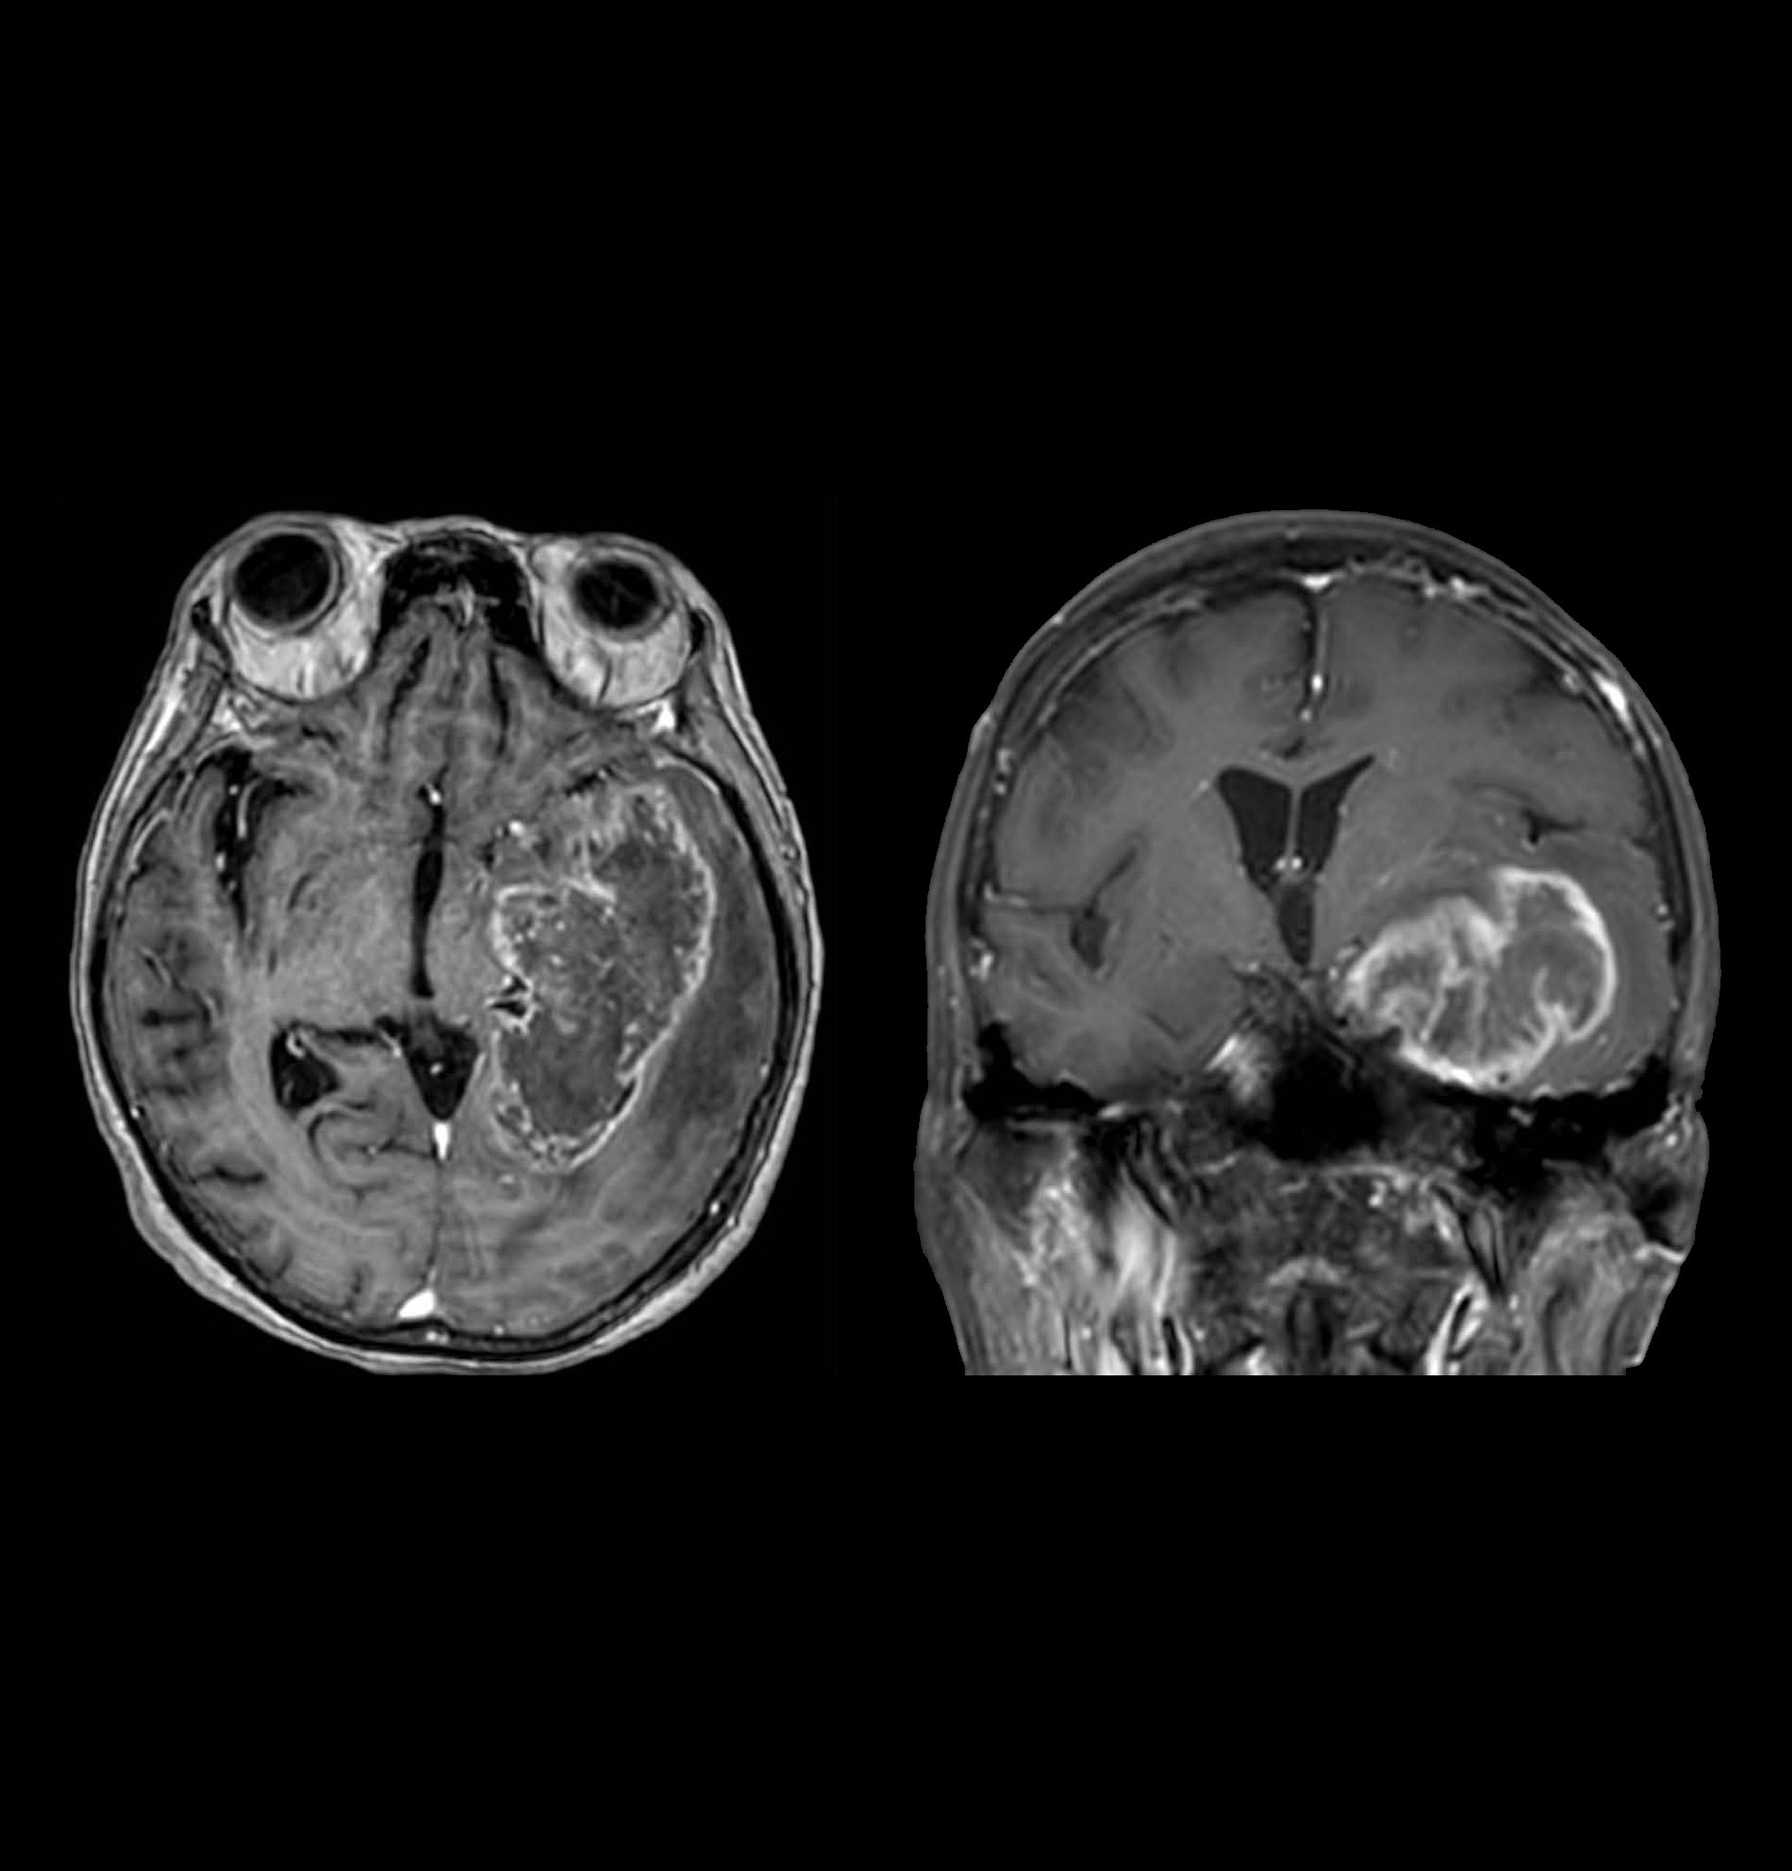

A Study Comparing Niraparib With Temozolomide in Adult Participants With Newly-diagnosed, MGMT Unmethylated Glioblastoma